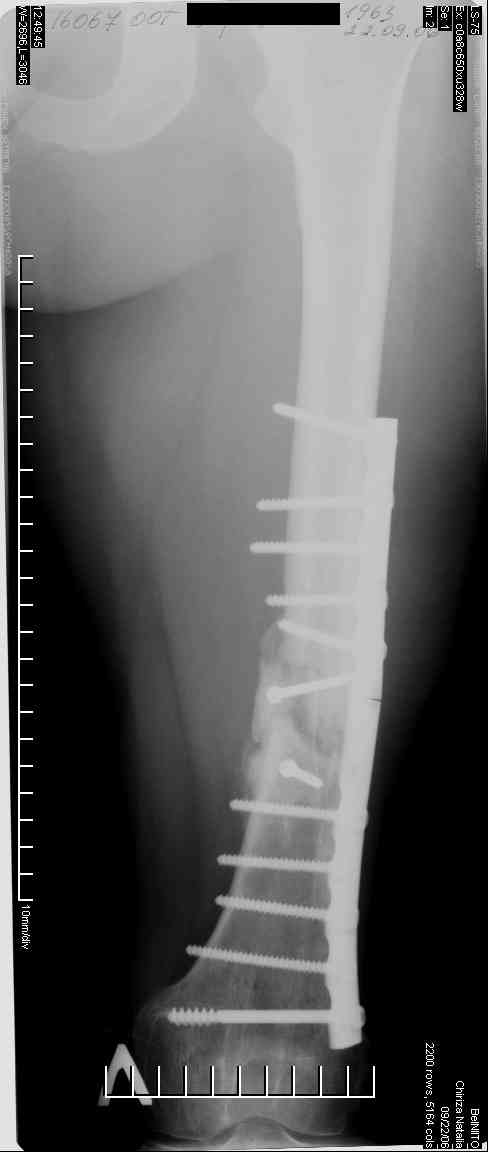

Соматически здорова. В ноябре 2004 года падение с высоты 12 м, перелом правой вертлужной впадины со смещением, неврит седалищного нерва, откр. перелом дистального отдела большеберцовой кости справа и закрытый перелом с/н/3 левого бедра. К нам поступила через 3 недели после травмы, был выполнен в 2 сессии сначала интрамедуллярный ретроградный остеосинтез бедра слева, затем остеосинтез вертлужной впадины и голеностопа справа. При остеосинтезе бедра пришлось немного приоткрыться в зоне перелома для репозиции и вообще операция затянулась часа на 2.5-3 (это один из наших первых интрамедуллярных синтезов). Через 4 месяца при нагрузке весом около 50 кг постепенно развилась варусная деформация бедра с искривлением стержня. Закрыто выпрямили под наркозом, динамизация гвоздя,но в сентябре 2005 г. согнулось бедро снова. Гвоздь удалили, остеосинтез пластиной, декортикация, пластика спонгиозой из метафиза б/берцовой кости. Динамика заживления вялая, но конструкция стояла неплохо (без признаков расшатывания), постепенно дали нагрузку - в марте 2006 года - перелом пластины - реостеосинтез пластиной, пластика гребнем подвздошной кости. На контролях (за август, т.е. 4 мес. после операции - прилагаю) динамика положительная, разрешена нагрузка до 50 кг. В начале этой недели без падения вновь появились боли в бедре - на Р-граммах - перелом пластины (снимки прилагаю). Фоном ко всему этому то, что и перелом вертлужки и дистального отдела б/б кости тоже не срастаются, хотя на голени уже дважды выполнялась костная пластика, на впадине - вторичное смещение, перелом части металлоконструкций. Исследовали гормональный фон - парат-гормон и прочие щитовидные в норме, месячные регулярно.Прошу совета по тактике дальнейшего лечения и выяснения причины тотального несращения всего сломанного.

Уважаемый Александр. Случай достаточно интересный, поскольку за 2 года,почему то ничего не срастается и все ломается. Жаль нет рентгенограмм таза и голени.Основными причинами несращения переломов бывает 1.не правильно выбранная тактика лечения, в том числе тактика оперативного лечения ( к примеру - не тот фиксатор, не того размера, неправильно установлен и т.д.)2.Девитализация костных отломков, а судя по рентгенограммам старались вы на совесть, когда открывали область перелома при интрамедуллярном остеосинтезе. Кстати, если это был не блокируемый остеосинтез, а обычный, то понятно почему стержень согнулся и нет сращения. На представленных рентгенограммах отдельные винты расположены даже с внутренней стороны, т.е. открылись вы качественно. 3.не правильно выбранная тактика лечения в п.операционном периоде или не выполнения больным данных рекомендаций. По бедру - мы бы убрали пластину и выполнили ретроградный блокируемый остеосинтез с рассверливанием. Если нет возможности, есть аппарат Илизарова. Но мороки и для вас и для больного много.

Винты с внутренней стороны кости фиксируют трансплантат, взятый из гребня подвздошной кости. Он довольно массивный и был уложен в дефект по передне-медиальной поверхности кости. тут уж пришлось действительно открываться на совесть.